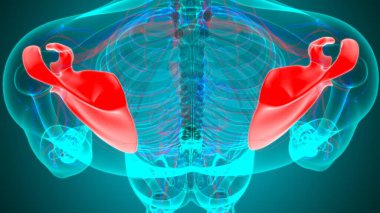

İnsan iskeleti anatomisi Scapula Kemiği Tıbbi Konsept için 3D Hazırlama

İskeletanatomiçene kemiğiyarım ayboyunlomberetmoidcapitateAltkısmınıHamate3d oluşturmaGöğüs kafesi3B illüstrasyoncarpalsağız sapımetakarplaralın kemiğiApendiküleruyluk kemiğioksipital kemikBurun kemiğikemiğigöğüs kemiğinin gövdesiayak kemikleriyarıçap kemiğiparietal kemikeksenel iskeletKalça kemiğilacrimal bonepalatine boneproximal phalangesinferior nasal conchaintermediate phalangesdistal phalangesclavicle bonekaval kemiğiBurun kıkırdağıkol kemiğikürek kemiğiBenzer İçerikler